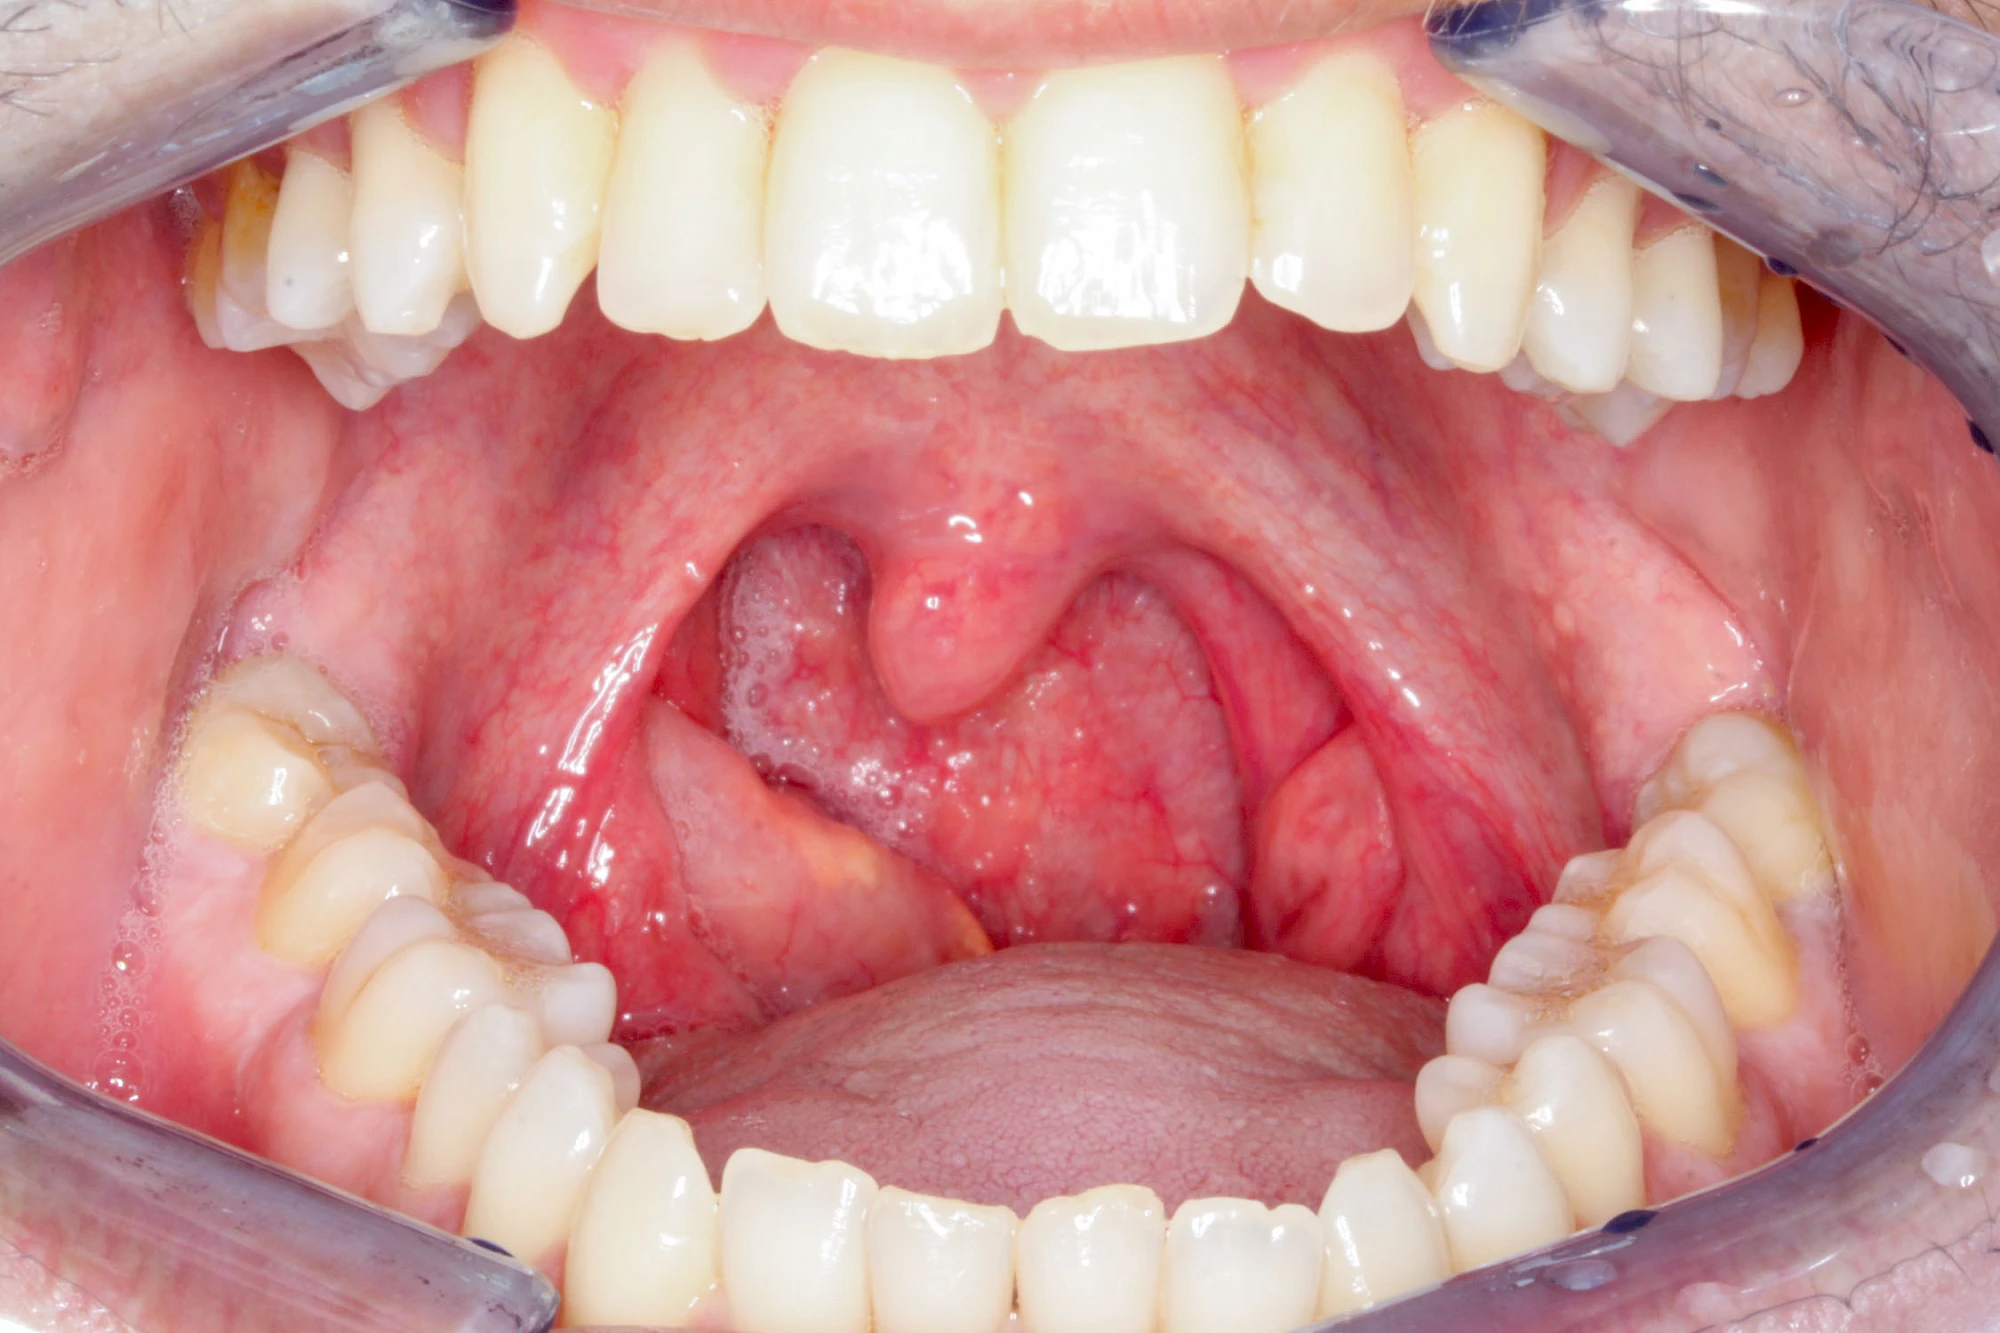

Mandelentzündung

Mandelentzündungen (Tonsillitis) zeigen häufig Rötungen, Schwellungen oder eitriges Sekret im Bereich der jeweiligen Mandel und sollten direkt ärztlich abgeklärt werden. Vielen Menschen wurde vor allem in der Kindheit ein- oder beidseitig die Mandeln entfernt, um die Atmung zu erleichtern. So können im Bereich der Gaumenbögen Vernarbungen oder Seitenunterschiede auffallen. Zudem können nach Mandelentfernungen (Tonsillektomie) die Infektanfälligkeit erhöht sein, da die Mandeln ja Bestandteil der Immunabwehr sind.

Bei Vergrößerung der Gaumenmandeln (Hyperplasie) z. B. infolge chronischer Entzündungenkann die Belüftung der Ohren gestört sein und es kann zu Schnarchen mit Atemaussetzern (Apnoe) sowie zu Schluckstörungen kommen. Bei entsprechenden Auffälligkeiten sollte eine ärztliche Abklärung erfolgen.